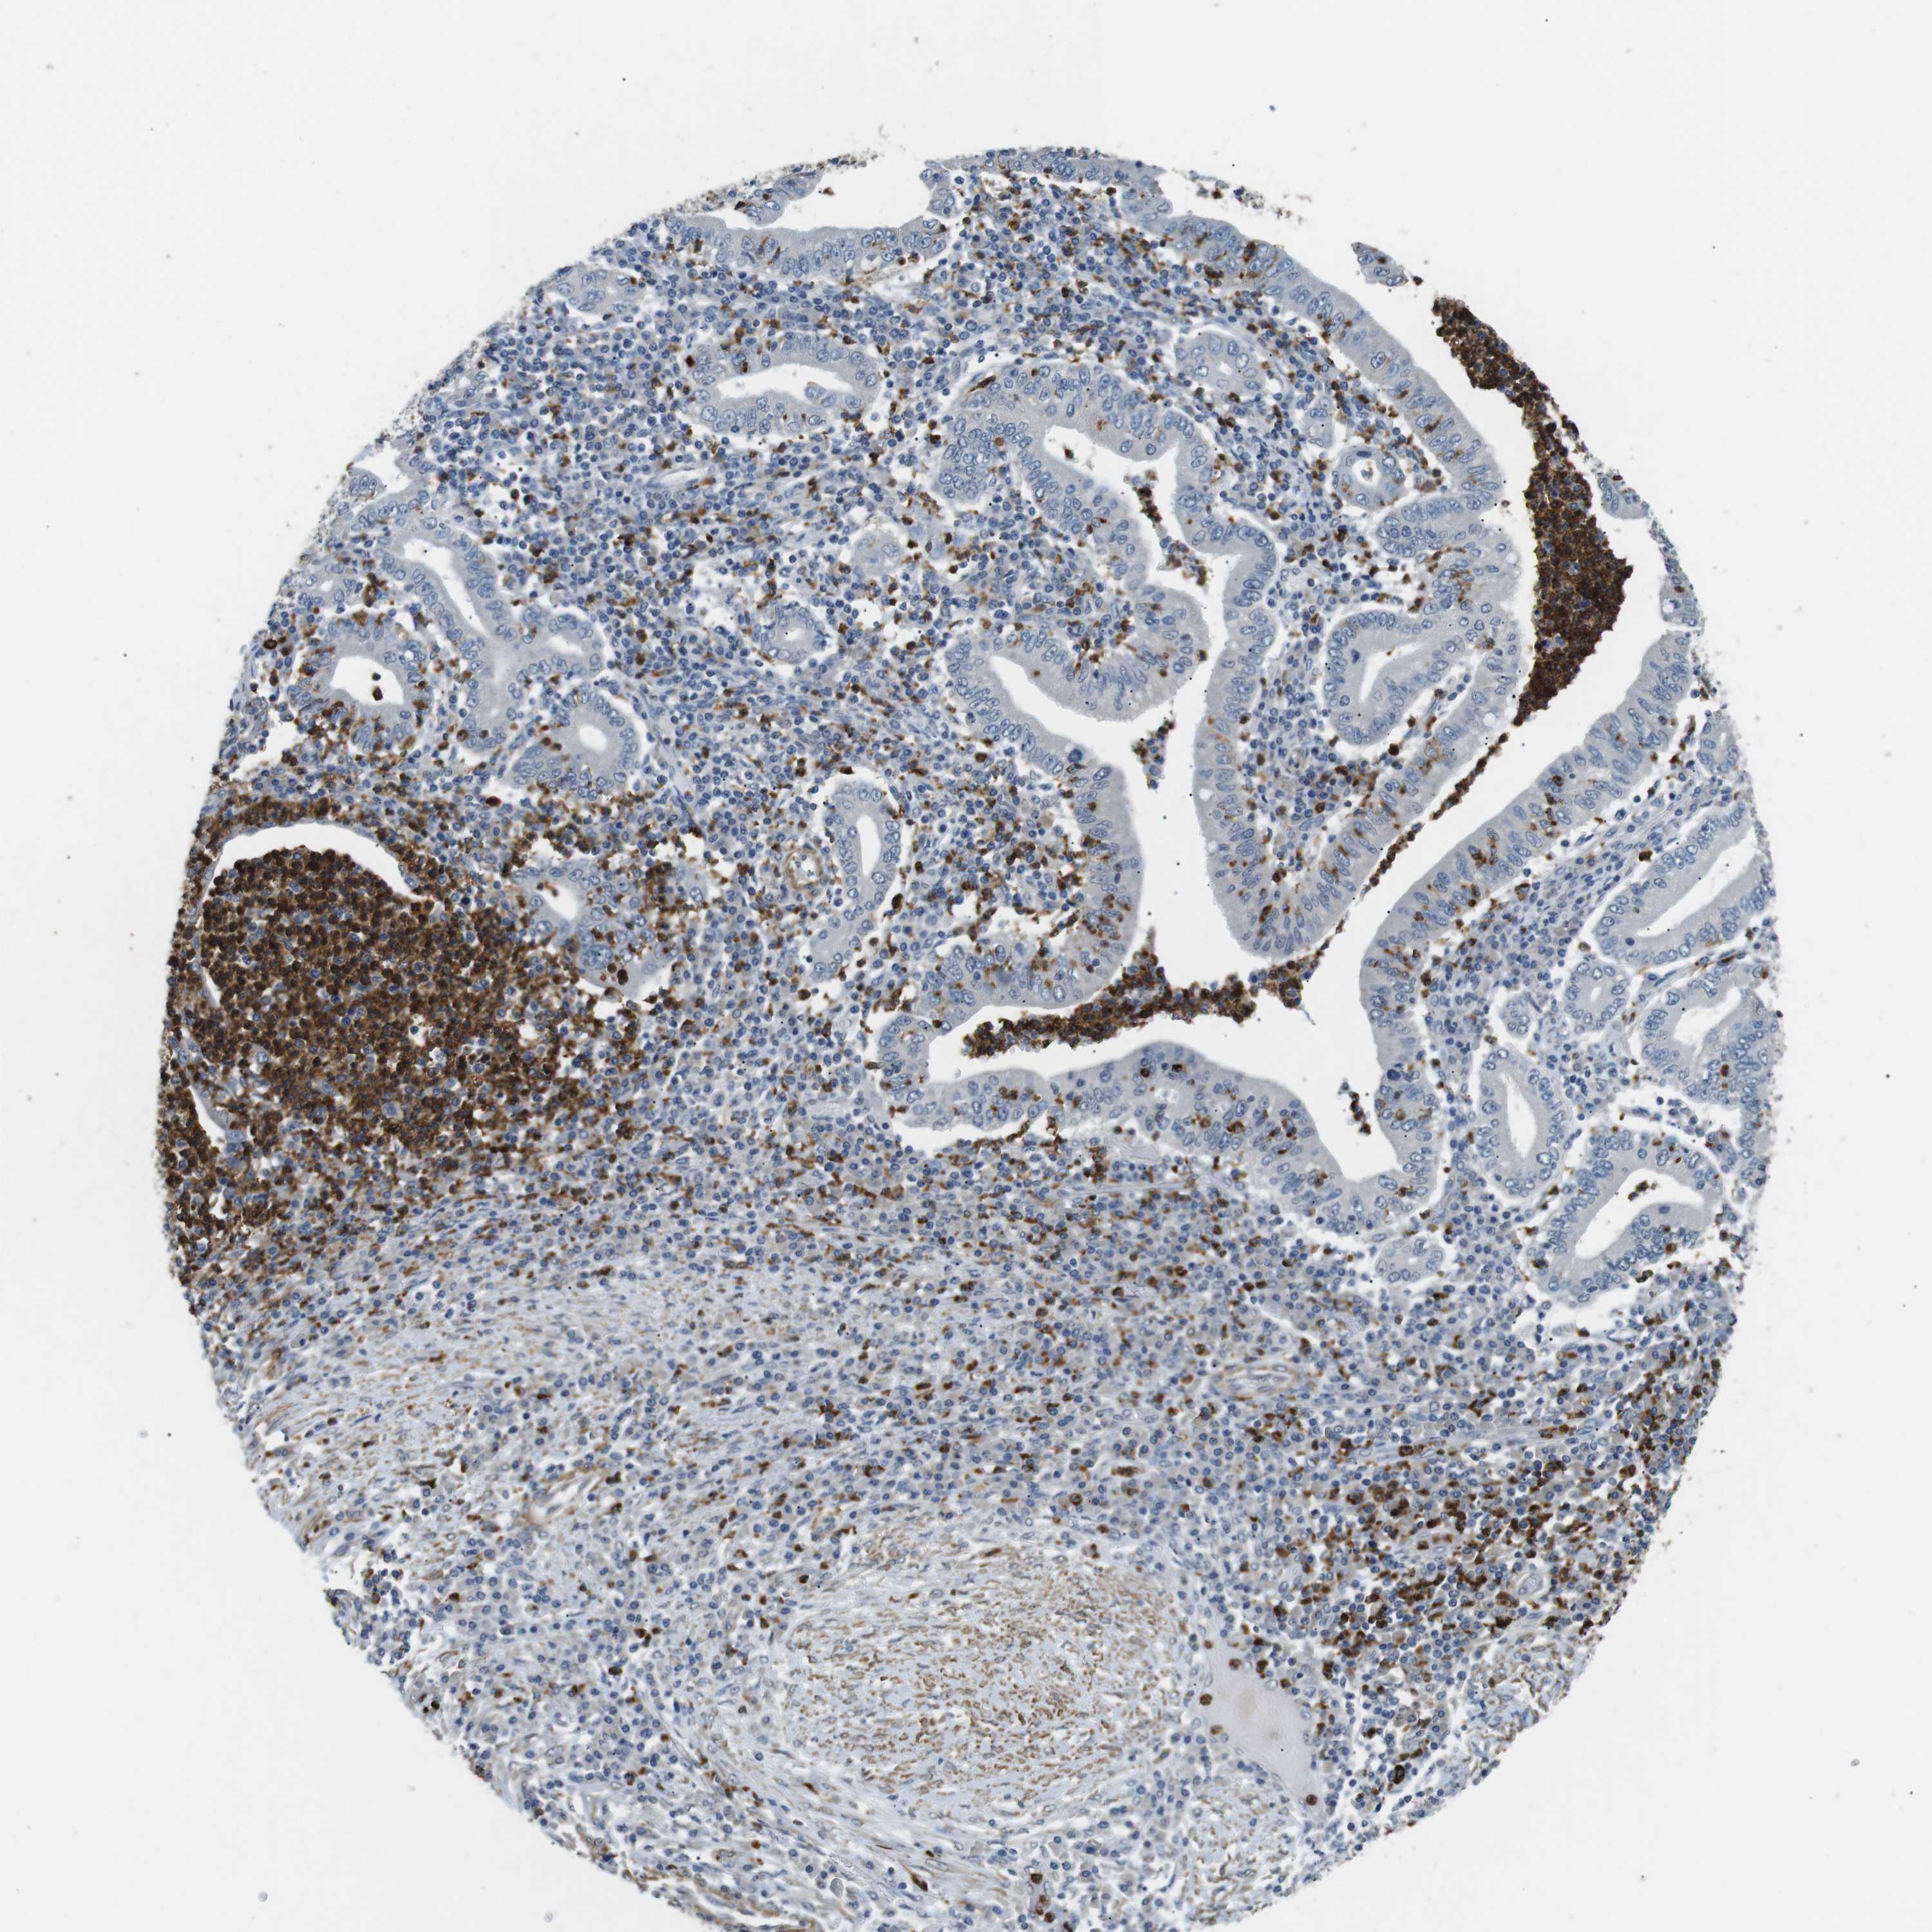

STOMACH CANCER - Protein expressioni

A mouse-over function shows sample information and annotation data. Click on an image to view it in a full screen mode. Samples can be filtered based on level of antibody staining by selecting one or several of the following categories: high, medium, low and not detected. The assay and annotation is described here.

Antibody stainingi

Antibody staining in the annotated cell types in the current human tissue is reported as not detected, low, medium, or high, based on conventional immunohistochemistry profiling in selected tissues. This score is based on the combination of the staining intensity and fraction of stained cells.

Each image is clickable and will lead to virtual microscopy that enables deeper exploration of all samples and also displays staining intensity scores, fraction scores and subcellular localization as well as patient and tissue information for each sample.

Antibody HPA015624

Staining

High

Medium

Low

Not detected

Intensity

Strong

Moderate

Weak

Negative

Quantity

>75%

75%-25%

<25%

None

Location

Nuclear

Cytoplasmic/membranous

Cytoplasmic/membranous,nuclear

Adenocarcinoma, NOS

Adenocarcinoma, High grade